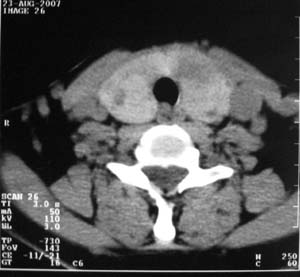

以下是引用zsl6918在2007-8-27 14:40:00的发言:[br]双侧甲状腺多发性低密度占位,边界清晰,密度欠均匀,尤以左侧明显,与周围组织分解清,考虑多发性腺瘤可能性大,不除外结节性甲状腺肿

以下是引用liaizhi在2007-8-27 15:20:00的发言:[br]双侧甲状腺散在多个囊性第密度影,左侧最大一个病灶与正常甲状腺分界尚可,气管受压稍右移。考虑甲状腺瘤的可能性大。